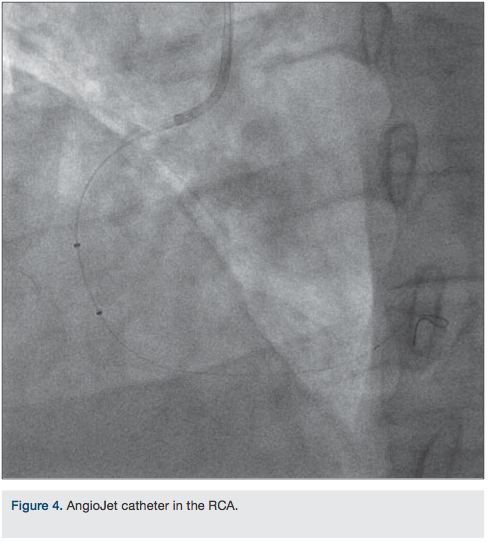

Coronary angiography revealed evidence of severe disease involving the left anterior descending coronary artery (LAD) and the circumflex artery. Right coronary angiography showed a totally occluded right coronary artery filled with a large thrombus (Figure 1). The right coronary artery was successfully cannulated with 0.14 Balance Middleweight (BMW) universal wire (Abbott Vascular) (Figure 2). An unsuccessful attempt was made to perform thrombectomy in the right coronary artery using a Pronto V3 extraction catheter (Vascular Solutions) (Figure 3). At this point, an AngioJet (Medrad/Bayer HealthCare) was inserted and

advanced into the right coronary artery to perform thrombectomy, in view of the large size of the thrombus (Figure 4). The distal end of the coronary wire was hooked up with the negative port of the pacemaker generator. The positive port was clipped to the patient’s skin for grounding. As expected, during the AngioJet procedure, the patient went into complete heart block and the pacemaker wire successfully paced from the right coronary artery as shown in Figure 5. Following the successful thrombectomy, two Xience stents (Abbott Vascular), 3.5 x